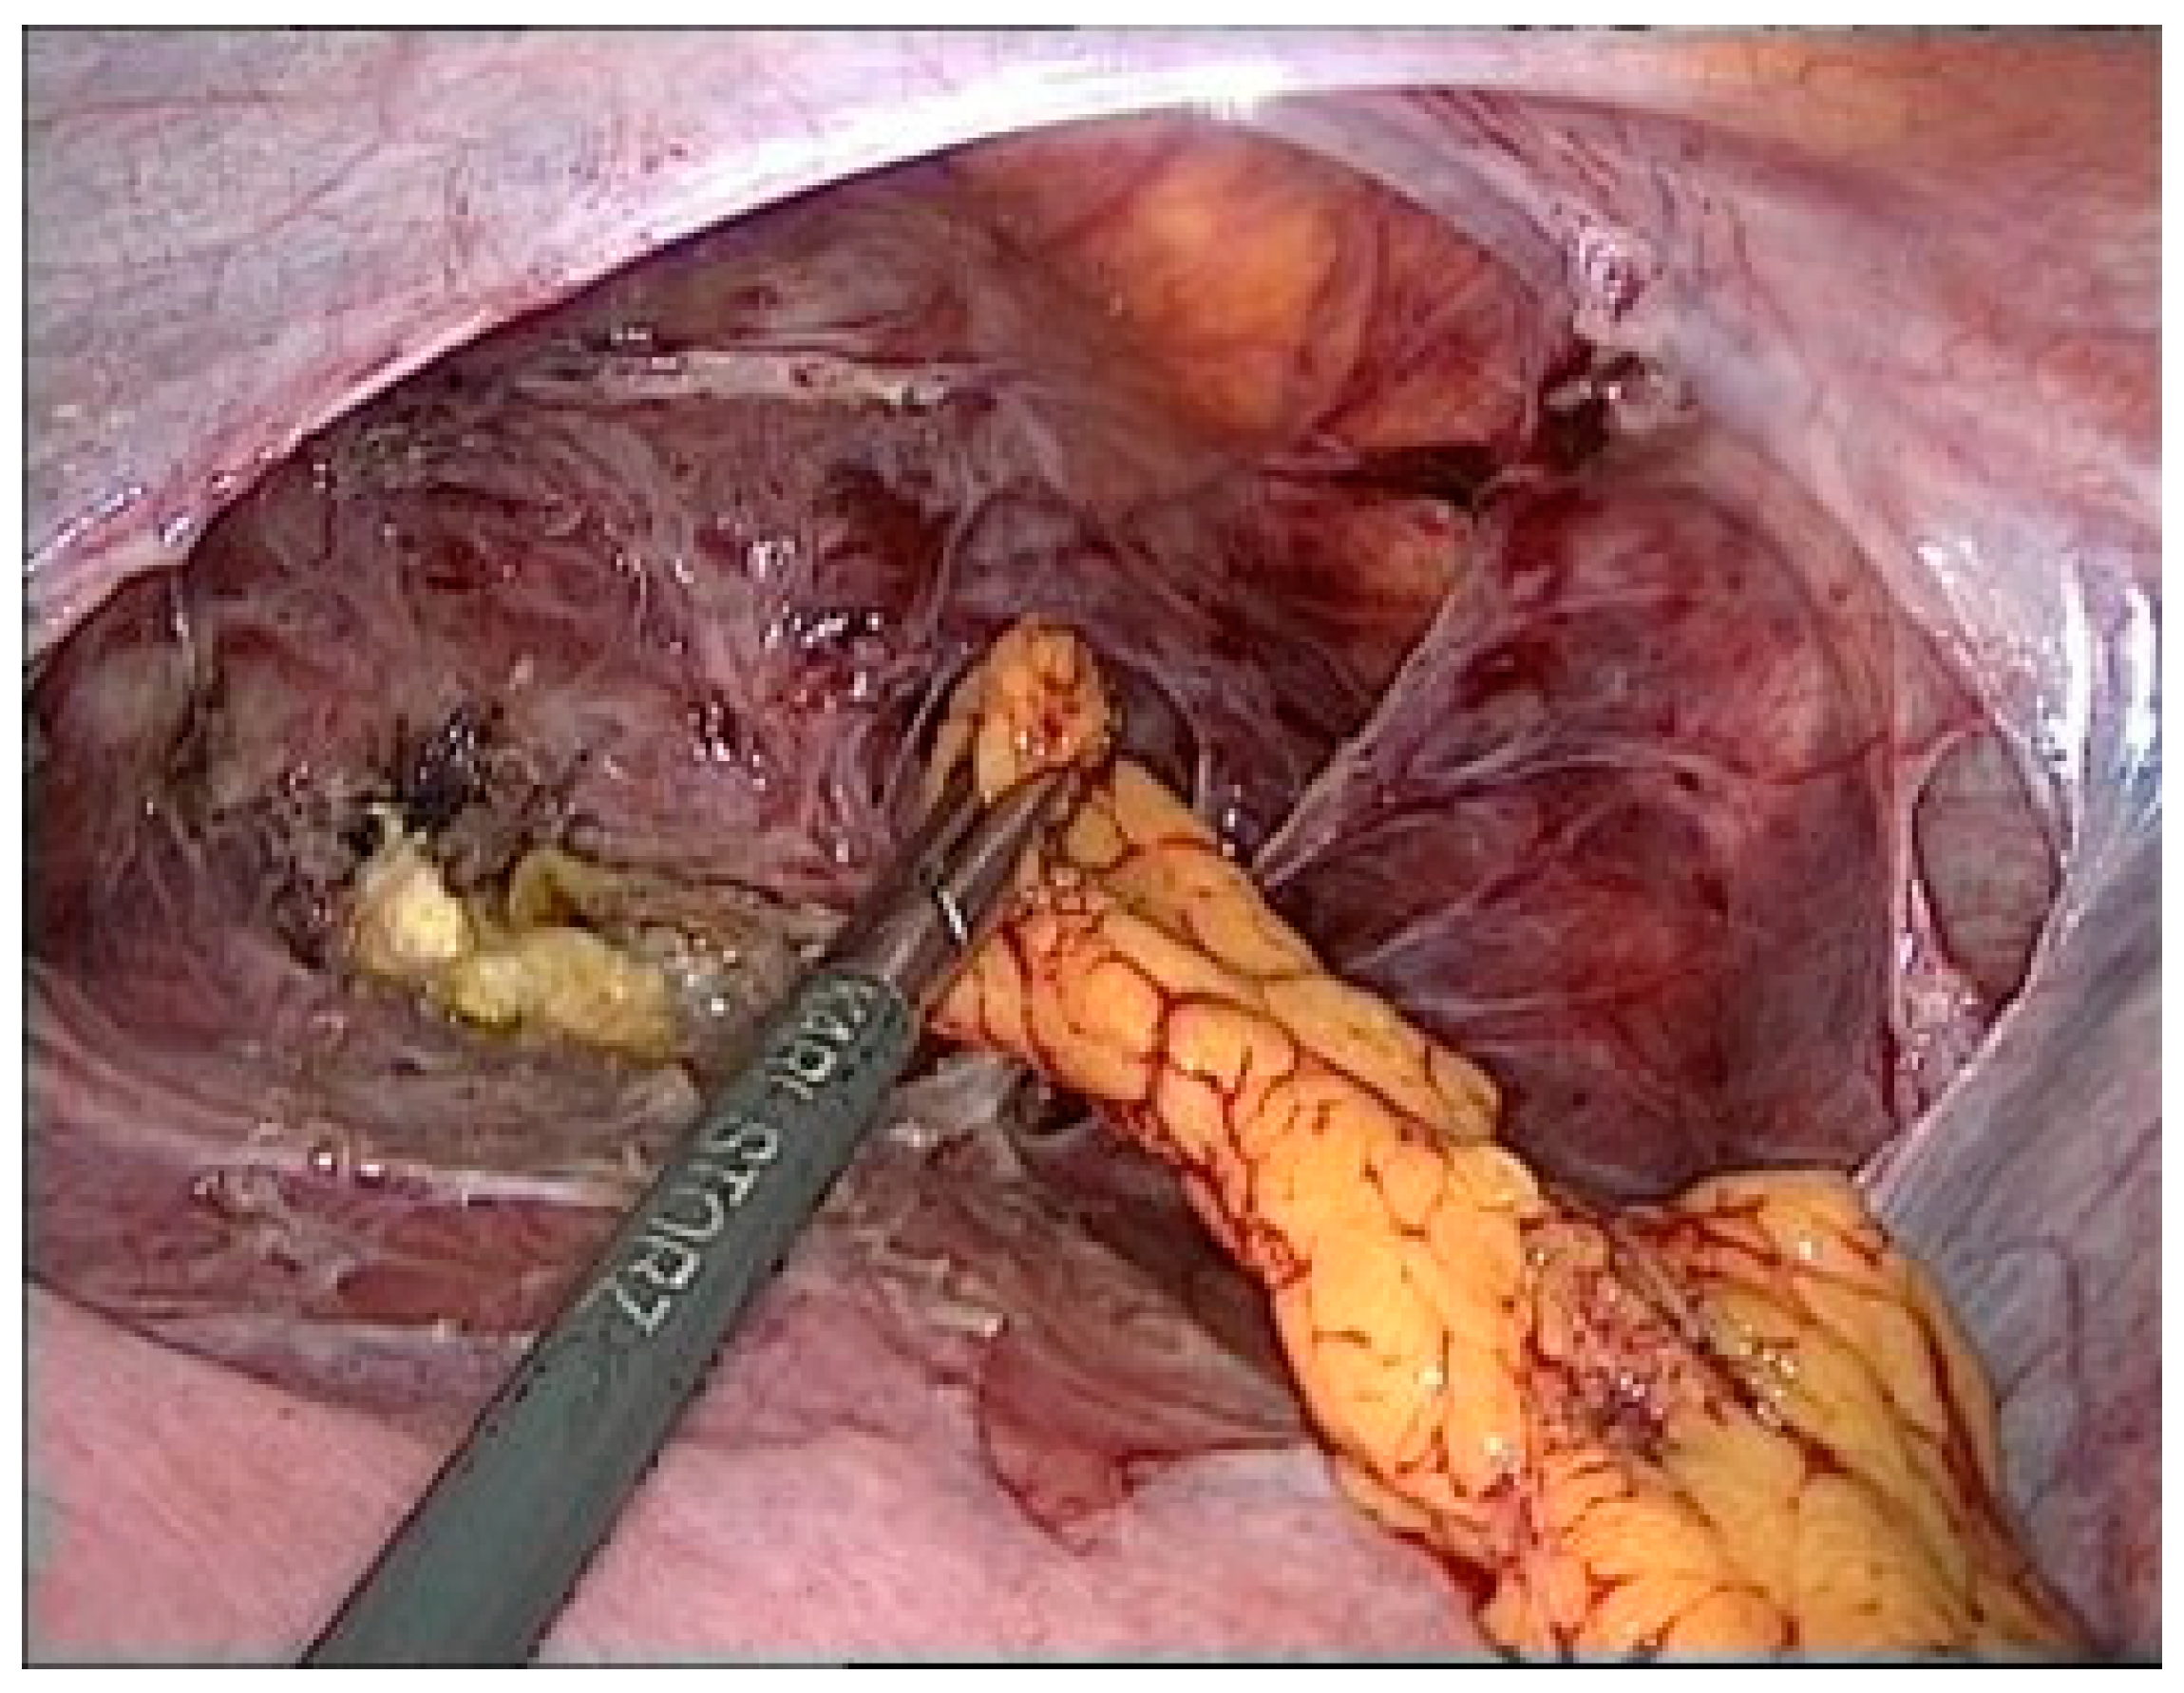

Due to the high symptom burden, the patient underwent surgery under general anesthesia via a minimally invasive laparoscopic approach. First, significant adhesions were observed between the urinary bladder and uterine body (Figure 2).

Figure 2.

Adhesion between the bladder and uterus (black arrow).

Adhesiolysis revealed a fistula between the urinary bladder and the uterus. The presence of sutures from a previous caesarean section most likely caused this abnormal communication. The abnormal tract between the two organs was removed using partial cystectomy, cystography, and partial myomectomy. Reconstruction was performed using a multilayer technique (Figure 3).